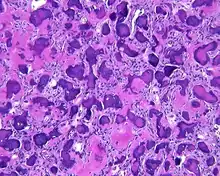

A hematoxylin and eosin stained slide show a cellular stroma with an innumerable psammoatoid calcifications

By microscopic evaluation, the tumors are composed of a variably cellular stroma make up of spindled to stellate fibroblast-like cells. Within this stroma, are numerous small, rounded, mineralized collagenous ossicles and immature osteoid. Many times the curved-shaped bone fragments have a collagenous rim around them. Ossicles may fuse to form much large mineralizations. Cementum-like psammomatous bodies (cementicles) may also be present. Osteoblastic rimming is not uncommon. Occasionally, giant cells and even mitoses are seen.[1][3]